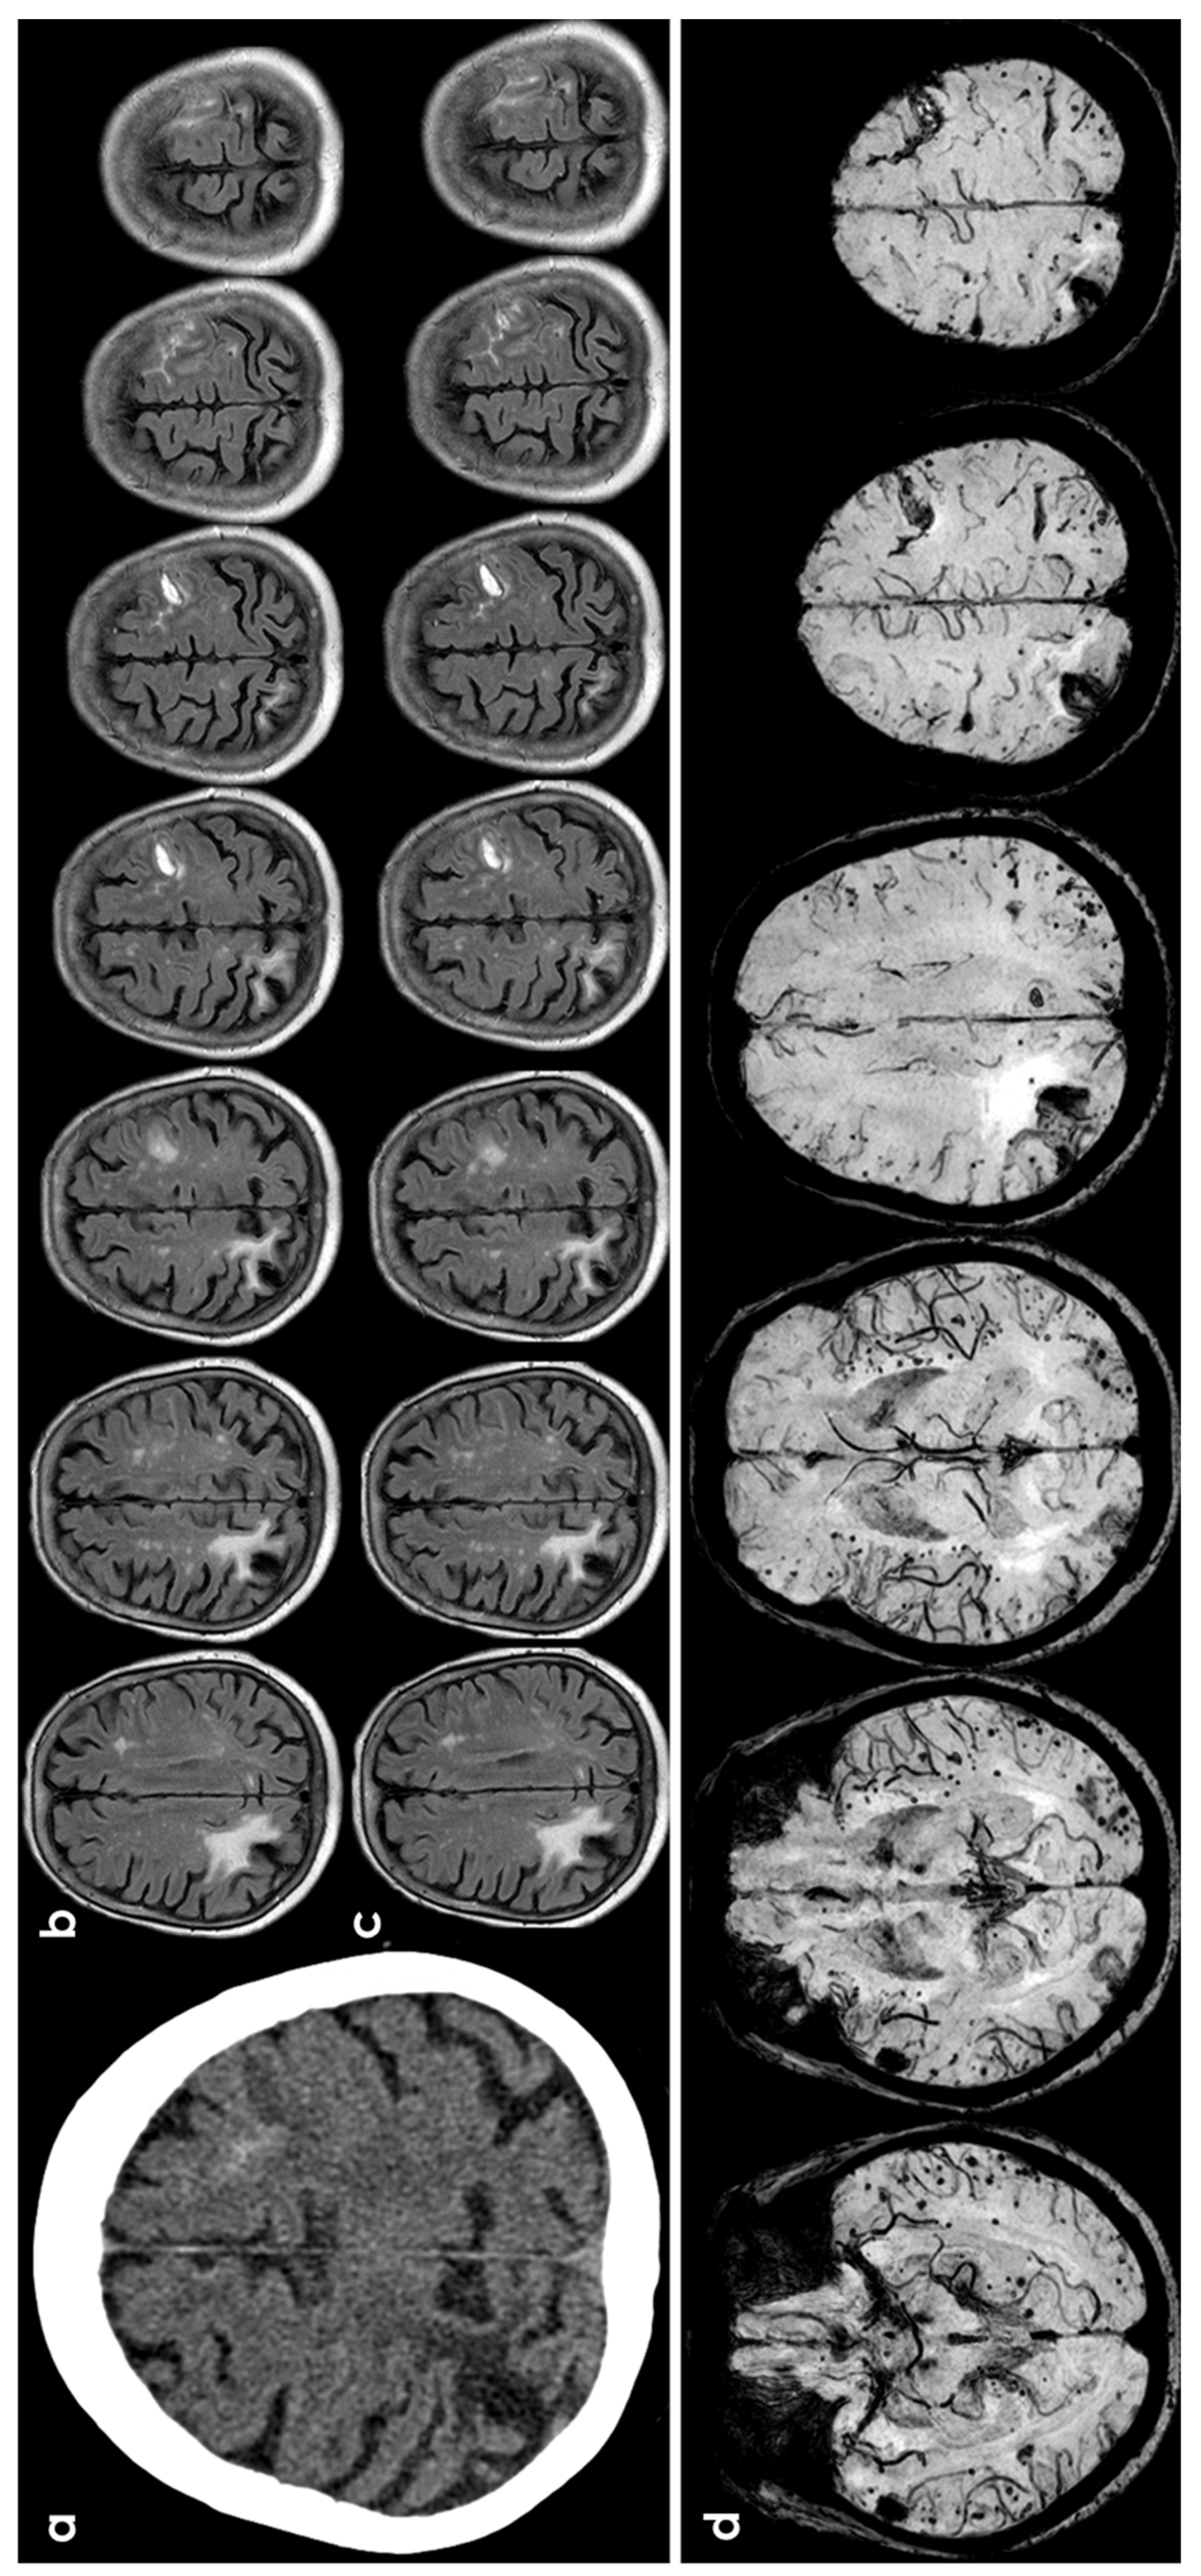

3.1. CAA

3.5. Primary Central Nervous System Angiitis

3.6. PRES/RCVS